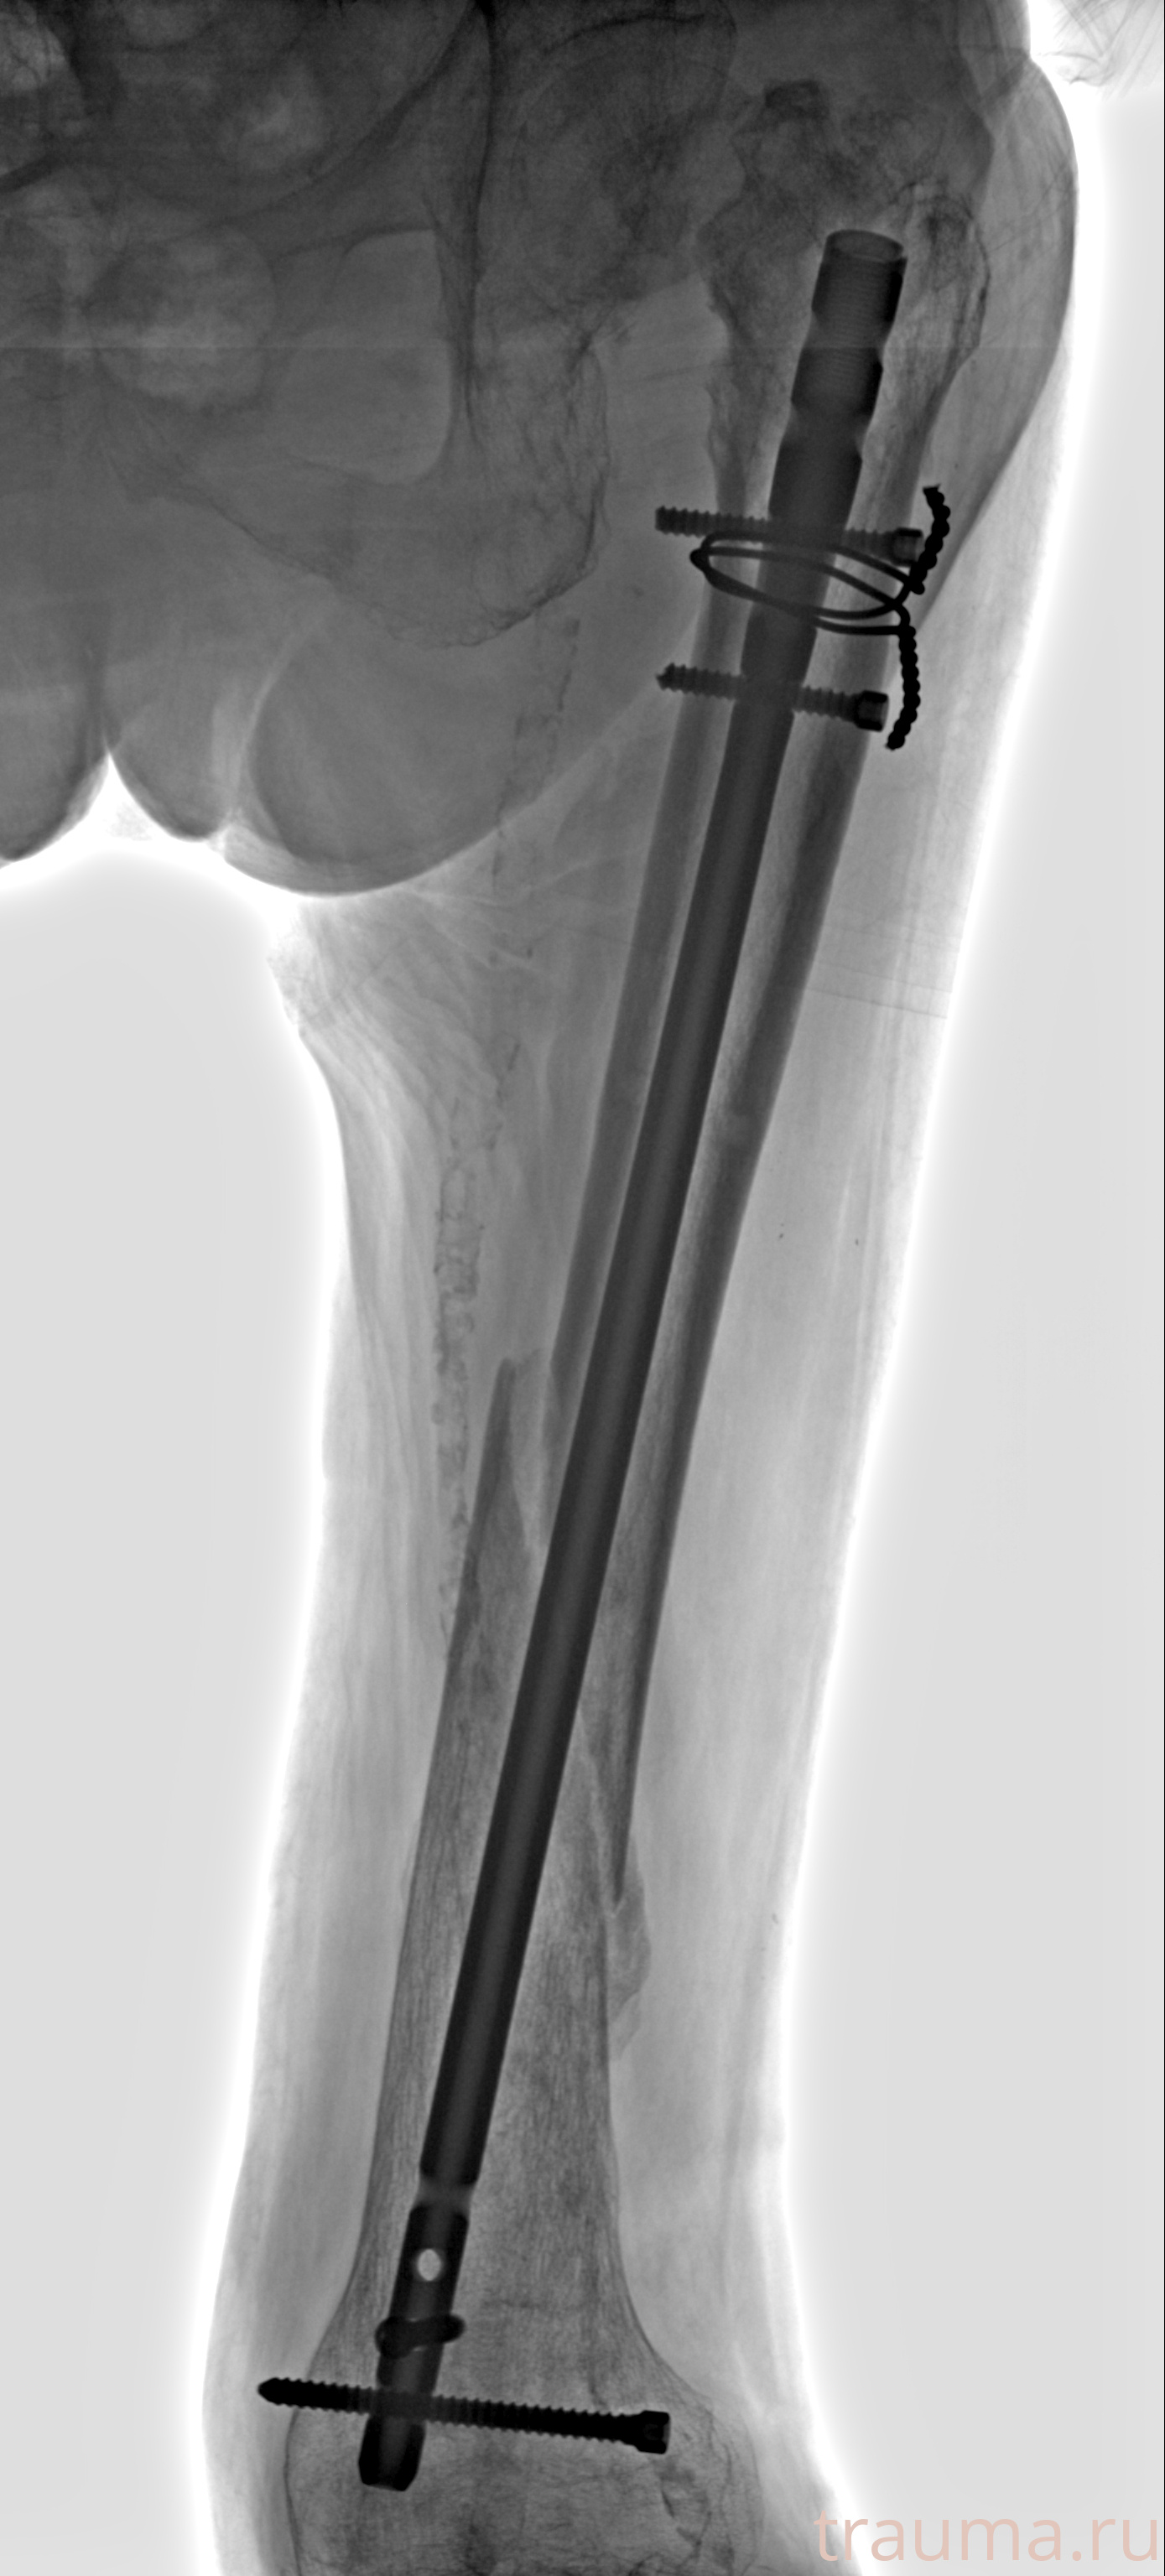

Рентгенограммы

Рентген на дому: по вашему адресу приезжает врач-рентгенолог, травматолог-ортопед с мобильным рентгеновским аппаратом, проводит диагностику травмы или заболевания, делает необходимые рентгенограммы, дает рекомендации по дальнейшему лечению. Получить качественные снимки в домашних условиях возможно благодаря уникальной методике, разработанной МосРентген Центром для института  Склифосовского